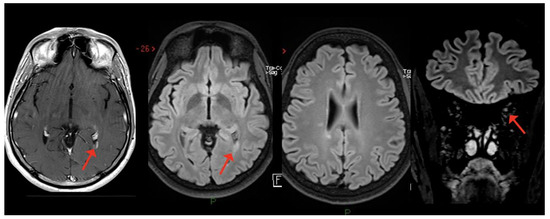

6. MS Diagnosis after COVID-19, with Probable Onset after SARS-CoV-2 Vaccines

| Case 1 | 2 weeks | BS (dyplopia) | - | + | + | - | +/+ |

| Moore et al. [52] | 2 weeks | BS (dyplopia) | BS, ST | + | + | NA | +/+ |

| Pignolo et al. [55] 1st case | 8 weeks | BS (facial palsy) | - | + | + | - | +/+ |

| Ismail et al. [76]. | 8 weeks | Cerebellum | - | + | + | - | -/- |

| Case 2 | 2 weeks | ON | - SC | + | - | - | +/+ |

| $ Case 3 | 2 weeks | ON | - | + | + | - | +/+ |

| Palao et al. [56] | 2 weeks | ON | ST | + | + | - | +/+ |

| Sarwar et al. [57] | 3 weeks | ON and unilateral motor deficit | ST | + | NA | NA | -/- |

| Case 4 | 4 weeks | SC | SC | + | + | + | +/+ |

| Fragoso et al. [58] | 6 months | SC | ST, SC | + | + | - | +/+ |

| Avila et al. [59] * | 2–6 weeks | 40% SC 40% ON 20% BS | NA | NA | + | 80% - 20% + | NA/+ |

| Feizi et al. [60] | 1 week | SC | SC | + | + | NA | +/+ |